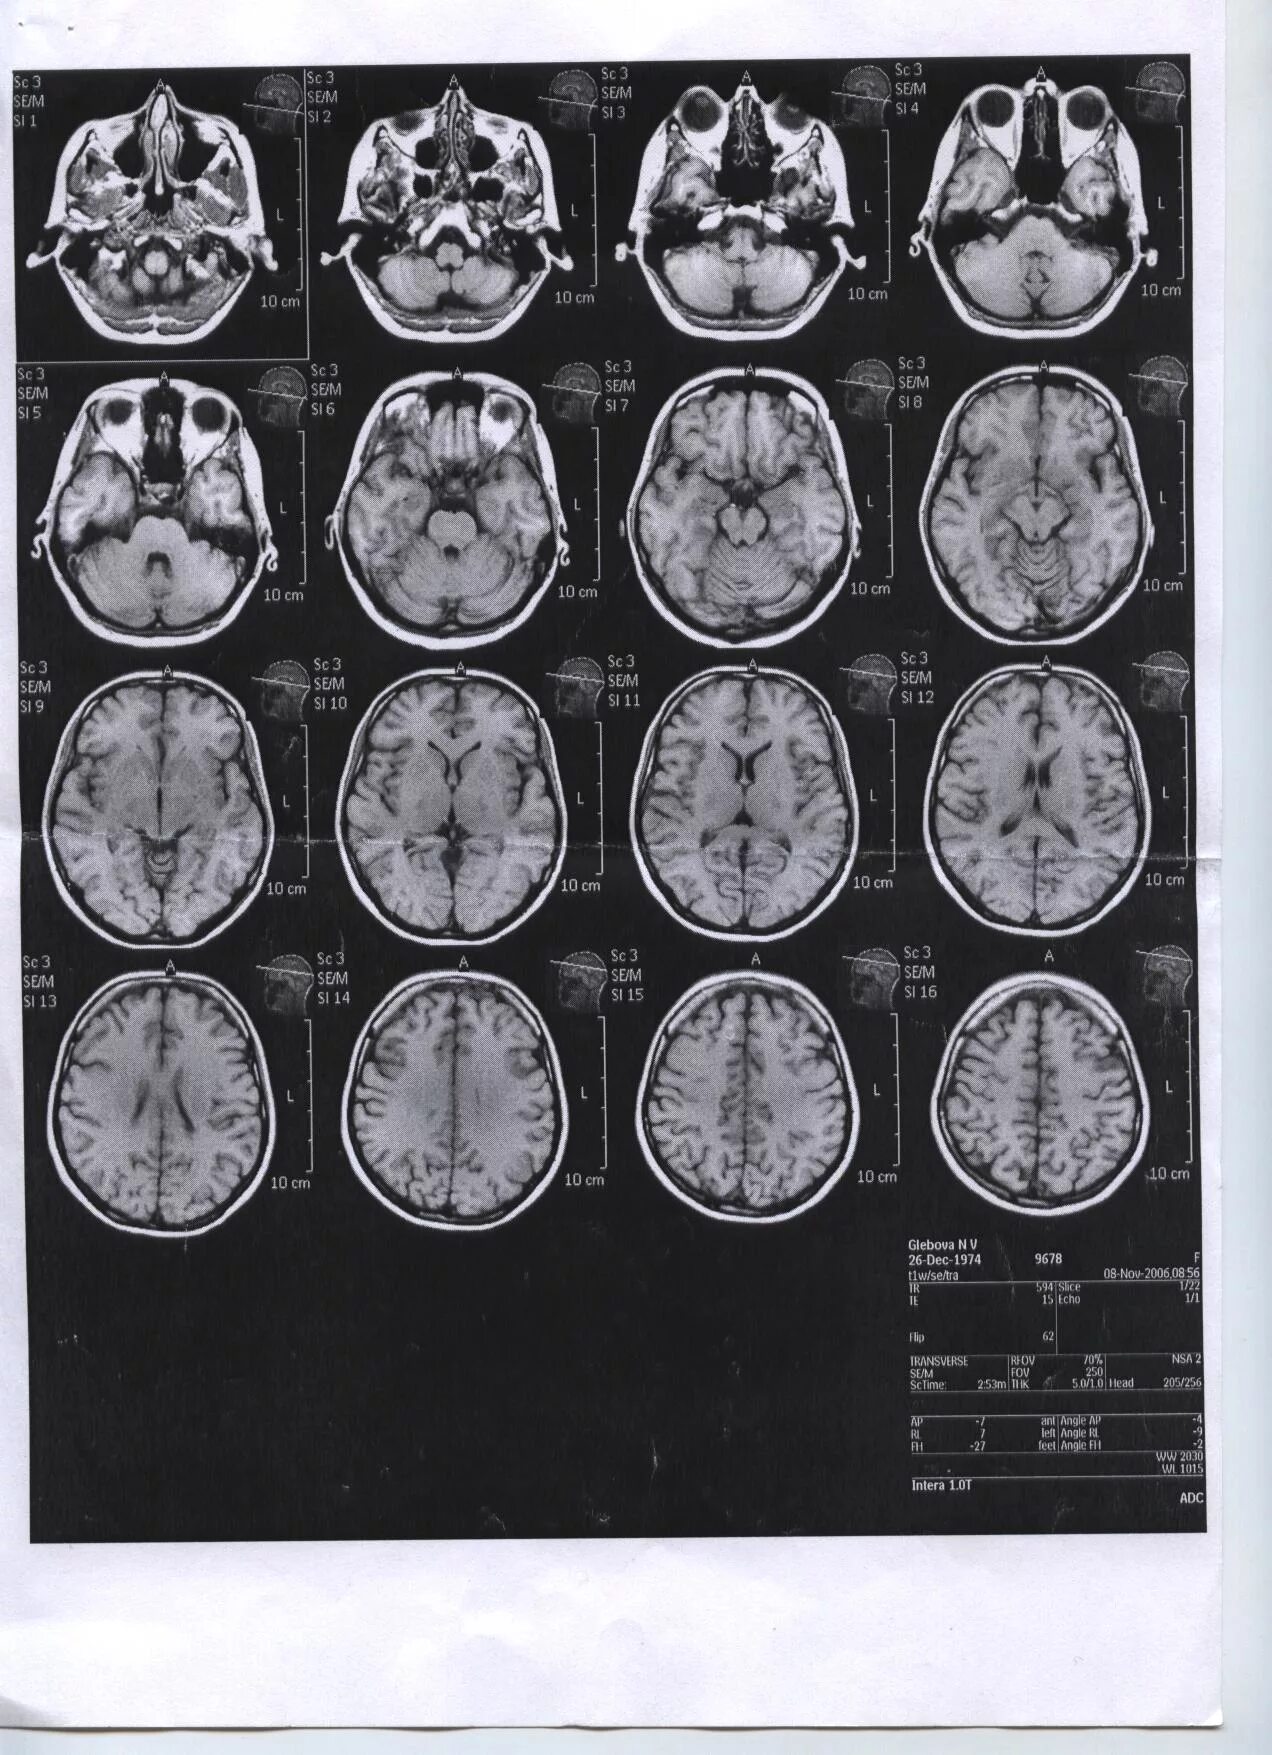

Что покажет мрт головного мозга с контрастом